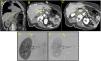

Mujer de 57 años con politraumatismo (precipitada desde un 7.° piso). Es hallada con GCS 13. Se realiza body-TC, apreciándose una HSA localizada en los surcos de ambos lóbulos temporales, fractura proximal del húmero y múltiples fracturas costales no desplazadas. Además, se objetiva un hematoma localizado en la región suprarrenal derecha de 7cm de diámetro (fig. 1A, círculo amarillo), conservándose un fino plano graso de separación con el hígado, pilar diafragmático, páncreas y riñón. En la fase arterial se aprecia extravasación activa de contraste (fig. 1B, flecha amarilla) compatible con hemorragia de origen arterial. La conservación de un plano graso entre el hematoma y las estructuras que rodean la suprarrenal (fig. 1C, círculo amarillo) permitió determinar el origen del sangrado. El conocimiento previo mediante TC del probable vaso lesionado acorta el tiempo necesario para realizar la arteriografía selectiva y posterior embolización de la lesión (fig. 1D, flecha amarilla). La arteria suprarrenal derecha fue embolizada con Glubran® 2+lipiodol (dilución 1:2), confirmando su oclusión completa y el cese del sangrado en el control angiográfico final (fig. 1E, flecha amarilla).